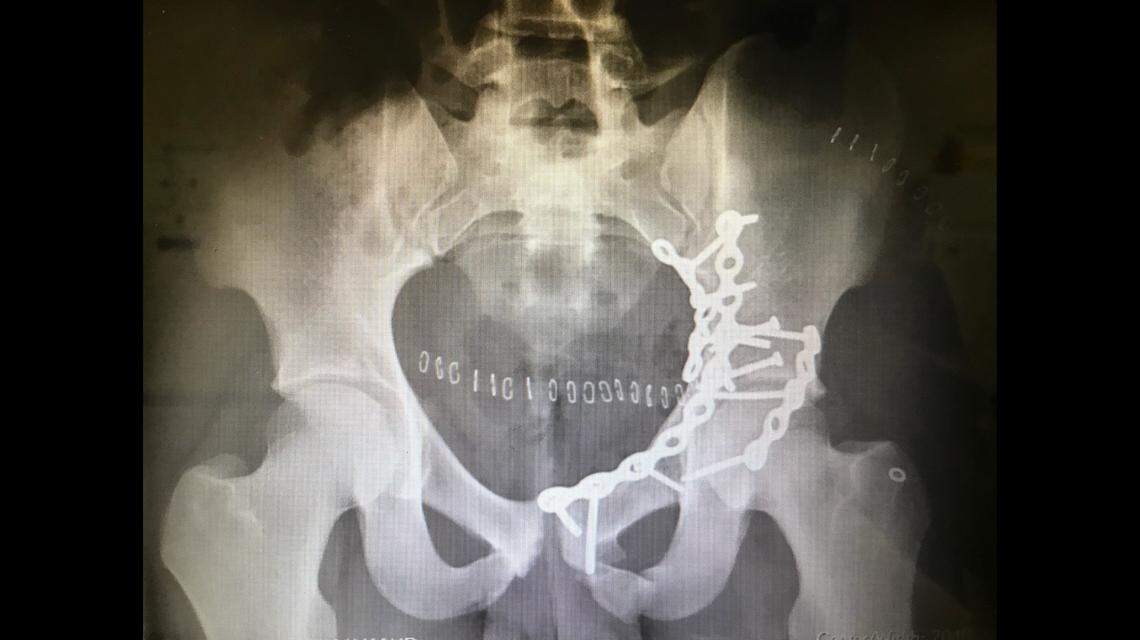

North Crowley senior Michael Hall broke his pelvis during a car accident in May 2020.

North Crowley senior Michael Hall broke his pelvis during a car accident in May 2020. Jessica Johnson Courtesy

When Hall woke up in the hospital, needles, tubes and wires were all around him, but he was calm. He broke his pelvis, jaw and right shoulder blade. He was in surgery for 10 hours.